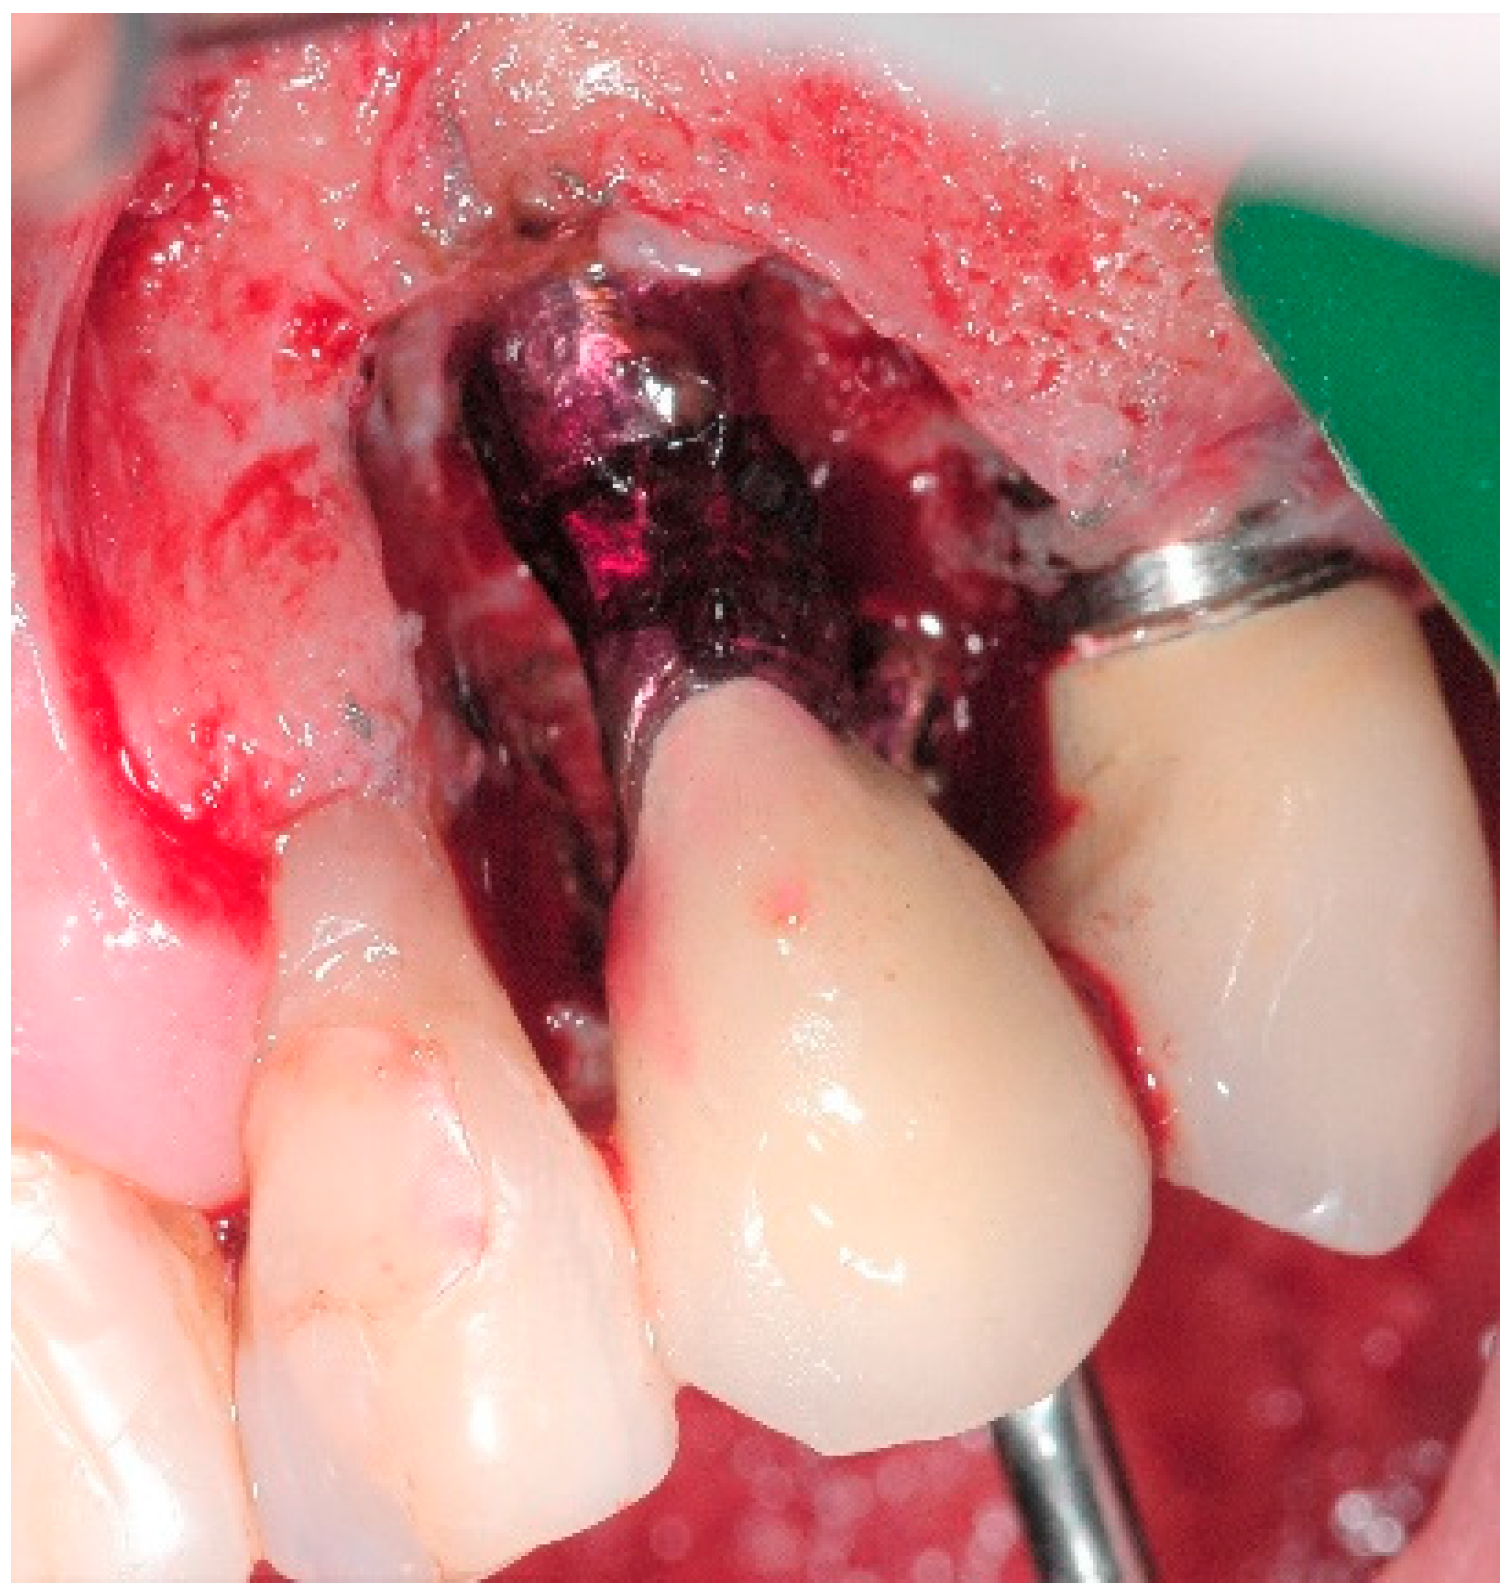

4.1. Surgical Procedure for Open Flap Debridement

4.2. Clinical Case